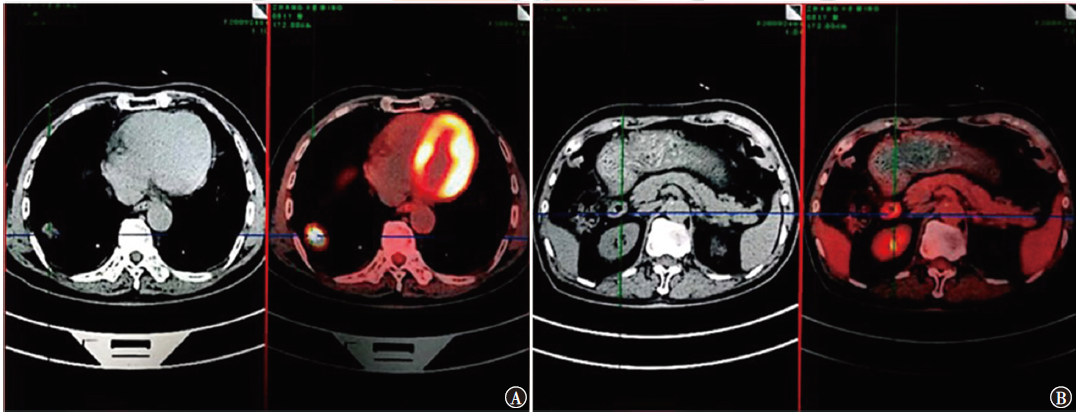

在非小细胞肺癌(NSCLC)的诸多驱动基因中,转染重排(RET)融合基因是一种新型突变基因,存在于1%~2%的NSCLC患者中。普拉替尼是一种RET抑制剂,用于靶向治疗RET融合阳性的NSCLC成人患者。现报道包头市中心医院收治的1例RET融合阳性NSCLC小肠转移老年患者的诊断过程、治疗方案及出现的不良反应,供临床参考。